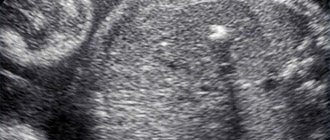

Вы пришли на второй скрининг, а Вам говорят, что у ребенка в левом желудочке гиперэхогенный фокус. «Гиперэхогенный» означает то, что на фоне тканей сердца участок обладает повышенной яркостью (плотностью). Феномен «гольфного мяча» возник по той причине, что такое гиперэхогенное включение по форме напоминает мяч, которым играют в гольф, и при сердечных сокращениях подпрыгивает cловно мячик. Чаще всего гиперэхогенный фокус (ГЭФ) обнаруживается в левом желудочке (ЛЖ), реже — в правом желудочке (ПЖ) и других камерах сердца. До сих пор остается загадкой, почему такой гиперэхогенный фокус (ГЭФ) в сердечной мышце, имеющий плотность костной ткани, бесследно исчезает после рождения.

1. Избыточное пропитывание солями кальция (кальциноз) определенного участка сердечной мышцы. Чаще всего такие изменения локализуются в области сосочковых (папиллярных) мышц. Второй триместр беременности, во время которого чаще всего обнаруживаются подобные изменения, характеризуется активной минерализацией опорно-двигательного аппарата ребенка.

2. Наличие дополнительной или ложной хорды в желудочке сердца ребенка. Такая ложная или дополнительная хорда не несет функциональной нагрузки, и не является патологией, а относится к малым аномалиям развития сердца (МАРС). Подобное явление — частая находка во время ультразвукового исследования. Сами хорды во внутриутробном периоде могут провоцировать отложение солей кальция, а также усиливать яркость гиперэхогенного фокуса.